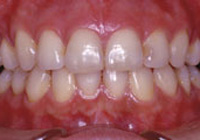

症例2:乱杭歯「歯並びが乱れている」

治療前 治療後